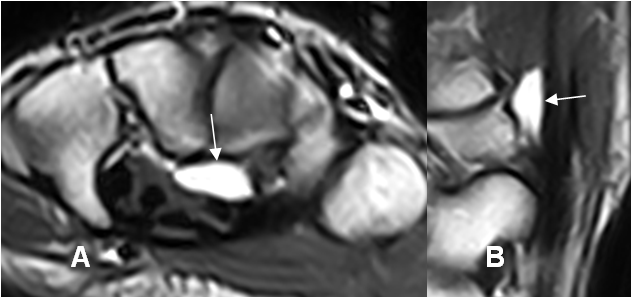

Fig 108 B. Ganglión quístico.

A: RM axial en T2 y B: RM sagital en T2. Imagen ovalada y de consistencia líquida, localizada por delante de los huesos del carpo, que corresponde a ganglión.